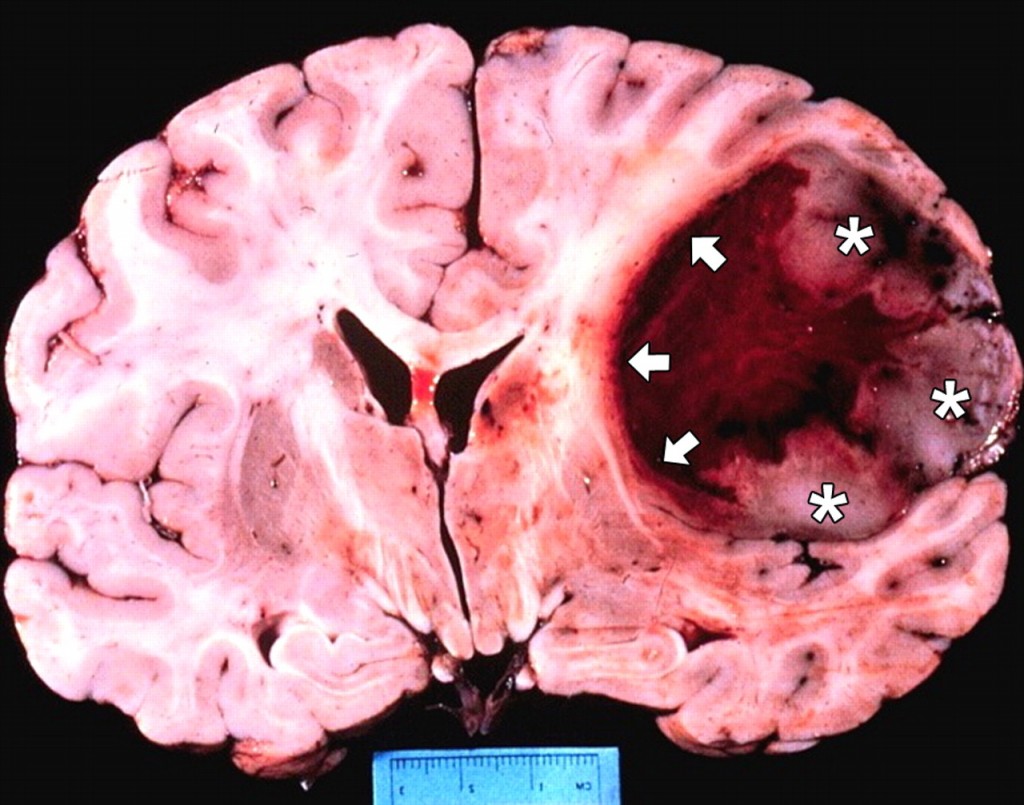

【藥源解析】GBMs是最常見(jiàn)的原發(fā)性腦瘤,平均生存期15個(gè)月。Rintega是針對(duì)EGFR一種叫做EGFRvIII突變型的疫苗,由13個(gè)氨基酸接在一個(gè)叫做KLH的載體蛋白組成,已經(jīng)獲得FDA突破性藥物地位。EGFRvIII突變?cè)?4-67%的GBMs有表達(dá)。去年在一個(gè)叫做ReACT的較小二期臨床試驗(yàn)中(73人),作為二線藥物Rintega和羅氏貝伐單抗聯(lián)用和單獨(dú)使用貝伐單抗比顯著改善PFS(11.6對(duì)9.3個(gè)月)。Celldex一度市值達(dá)到20億美元。更有投資者預(yù)測(cè)如果ACT IV成功Rintega可能同時(shí)被批準(zhǔn)用于一線和二線GBMs,Celldex市值可達(dá)8億美元。

GBMs是預(yù)后較差的中樞腫瘤,而且高度異化。雖然~30%有EGFRvIII變異,但腫瘤似乎很容易找到逃逸路線。GBMs的腫瘤微環(huán)境有很多免疫抑制機(jī)制,令疫苗作用有限。治療性腫瘤疫苗是一個(gè)成功率較低的治療手段,和已經(jīng)確證的機(jī)理比較(如EGFR抑制劑)所觀測(cè)到的陽(yáng)性數(shù)據(jù)更可能是假陽(yáng)性。所以同樣是積極的二期臨床結(jié)果,這些創(chuàng)新程度更高的療法風(fēng)險(xiǎn)更大,當(dāng)然如果成功回報(bào)也會(huì)更大。